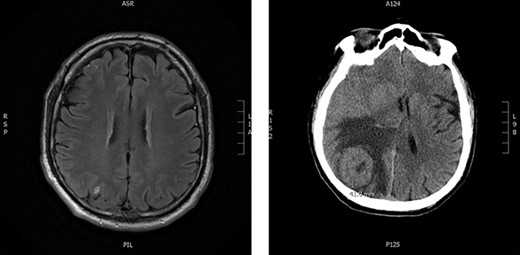

Upon re-presentation in 2019, workup included brain magnetic resonance imaging (MRI), positron emission tomography (PET) scan and re-biopsy. Brain imaging revealed a 6 mm solitary right parietal brain metastasis (Fig. 3). On PET scan, the tumour exhibited mild FDG uptake, with the SUV max of 2.9 (Fig. 4). There was no evidence of nodal or distant metastatic disease. Biopsy again was consistent with SFT. The patient was reviewed at Multidisciplinary Thoracic Tumour Board Rounds. Considering the large size and compressive effects of the pleural-based tumour, combined with the small size and asymptomatic nature of the brain lesion, it was determined that the optimal approach would be surgical resection of the left-sided pleural SFT and active surveillance of the brain metastasis. The patient underwent complete en bloc resection of the tumour via left thoracotomy including the eighth rib, partial pleurectomy and a left lower lobe wedge resection to achieve an R0 resection (Fig. 5).

Brain imaging; solitary right parietal brain metastasis measuring 6 mm August 2019 (left) and 4.5 months later measuring 4.1 cm (right).

Approximately 1 month after discharge from the initial procedure, the patient presented acutely with left hemiplegia. MRI of the head demonstrated significant growth of the right parietal lesion, now 4.1 × 4 × 3.5 cm, with new surrounding edema (Fig. 3). The patient underwent a right parietal craniotomy with gross total resection of the lesion and adjuvant radiotherapy to the brain (60 Gy in 30 fractions). Pathology confirmed the diagnosis of metastatic SFT.